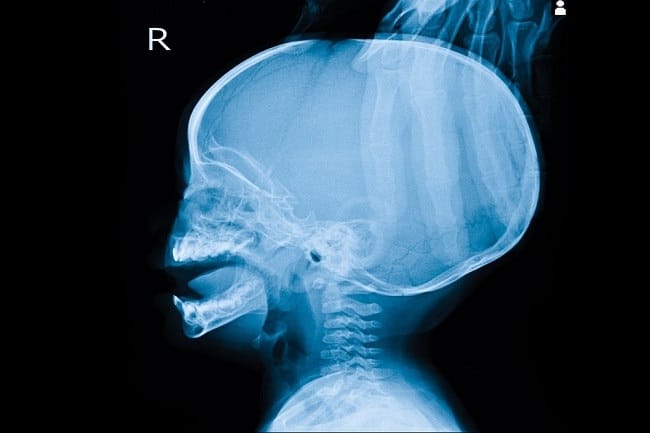

Dokter akan melakukan pemeriksaan meliputi USG, CT scan, dan MRI kepala untuk mengetahui penyebab penyakit kepala besar. Setelah mengetahui penyebabnya, dokter akan memberikan penanganan yang sesuai, antara lain: